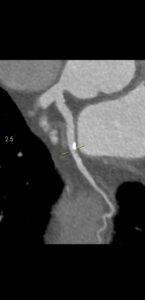

Video 2: Radioscopie la 2 luni postoperator (pacient detubat, dar ventilat non-invaziv): mișcare paradoxală a diafragmului stâng, cu ascensionare în inspir. Tulburări de ventilație pulmonar bilateral decliv, dar mai extinse de partea stânga.

Examenul fluoroscopic al diafragmei (testul mirosului „sniff test”) este util în diagnosticarea paraliziei diafragmatice. La indivizii normali, ambele hemidiafragme coboară de obicei cu inspirație. În cazurile de paralizie diafragmatică unilaterală, partea afectată poate demonstra o mișcare ascendentă paradoxală.

Ecografia este un bun înlocuitor pentru fluoroscopia și poate fi efectuată la pat cu pacientul întins, dacă poate respira în această poziție. Este mai ușor să evaluezi copiii cu ultrasunete cu evitarea riscul de iradiere. Ecografia în timp real este efectuată în plan axial pentru a compara cele două hemidiafragme simultan. Modul M suplimentar coronal sau sagital poate ajuta la cuantificarea gradului de mișcare a fiecărui hemidiafragm individual. Criteriile de diagnostic la copii includ mișcarea paradoxală, excursia mai mică de 4 mm și o diferență >50% între excursia unui hemidiafragm față de celălalt.